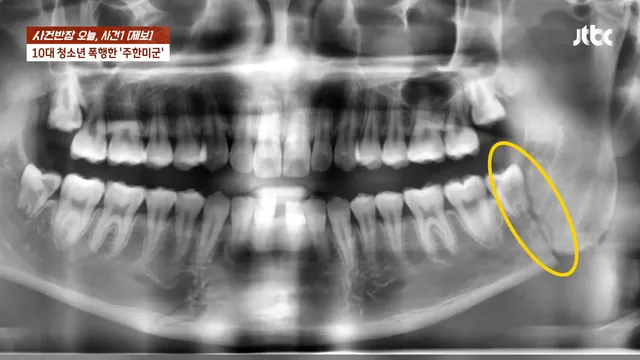

주한 미군 주먹에 10대 학생 ‘턱뼈’ 부서져

아니 어떻게 턱뼈가 저렇게 부셔지냐 ㄷㄷㄷ

턱뼈가 4군데 부러졌는데 의사도 사람이 때린게 맞냐며 의사하면서 주먹으로 이렇게 턱관절 골절된건 첨봤다고 함 ㄷㄷ